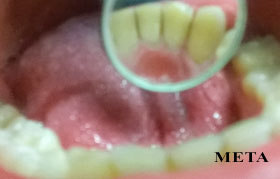

PHOTO GALLERY